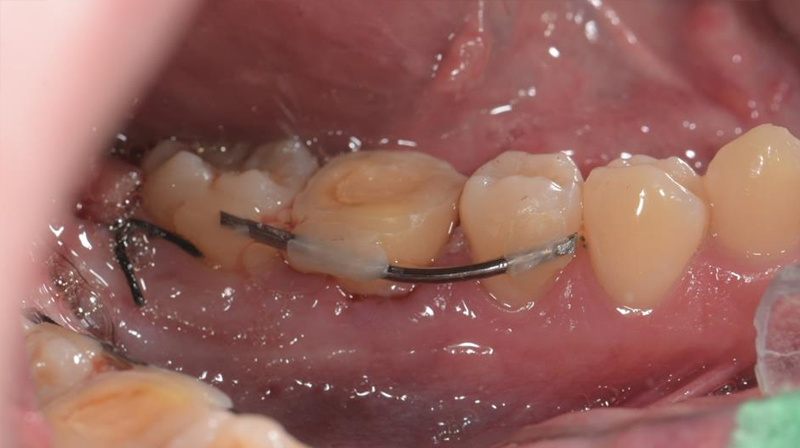

拔除智齒,固定至第一大臼齒缺牙區域

智齒固定